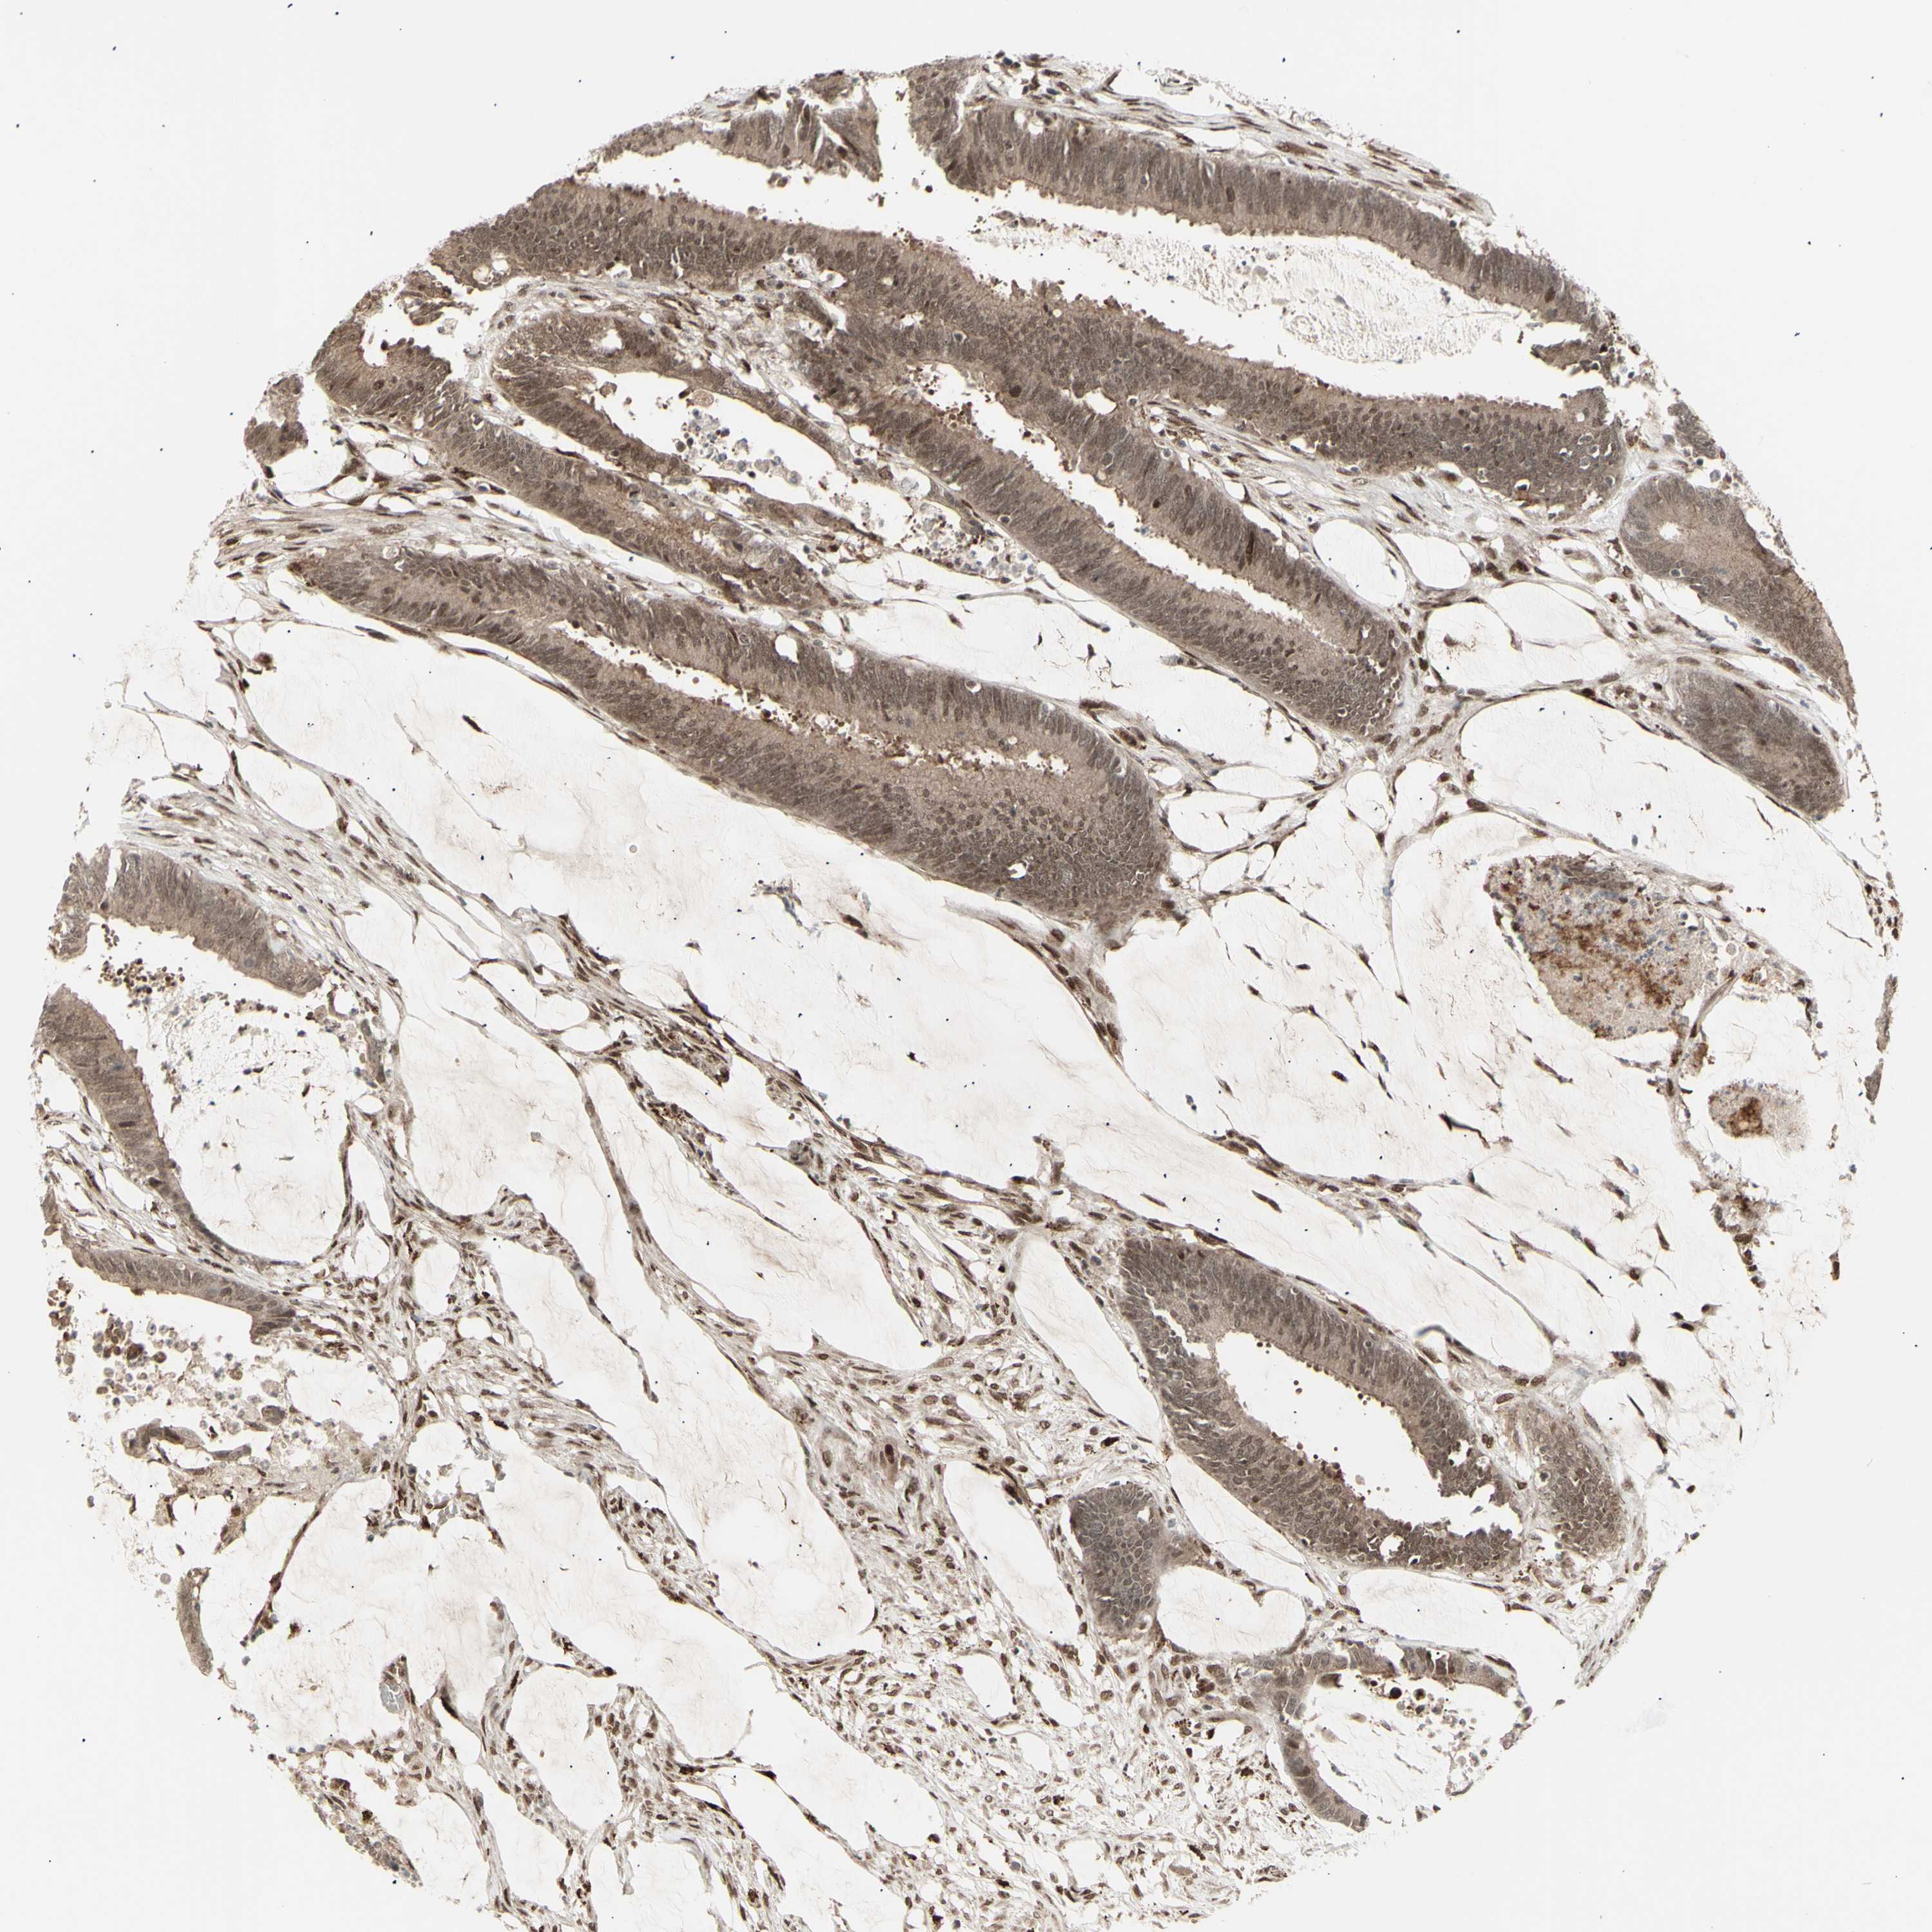

CBX1

CANCER COLORECTAL CANCER Show tissue menu

Colorectal cancer

Rectum adenocarcinoma